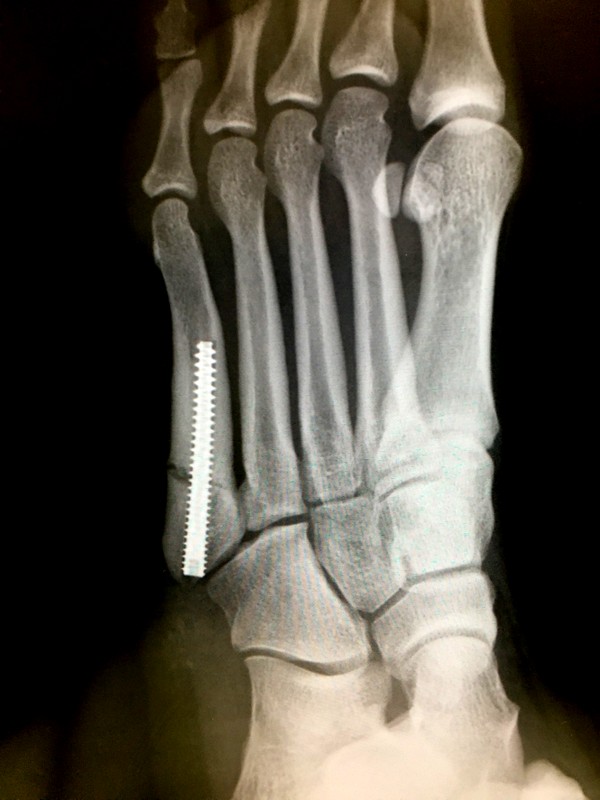

2020年年明けに左足の第五中足骨を骨折しました。結論から言うと手術し骨にボルトを埋め込みました。手術の結果、痛みが小さくなり運動等ができるようになりました。一方で折れた骨は骨片がくっついて再生することなく離れたままの状態で安定しました。治療期間約3か月、ここでは骨折.. 第5中足骨骨折とも呼ばれているジョーンズ骨折は、ジャンプによる動作やランニングなどのスポーツシーンに起こりやすい障害のことを言い、一般的な骨折に比べると自覚症状が出にくいケースがあります。 今回はジョーンズ骨折(第5中足骨骨折)の原因や主な治療法、症状や経過だけでなく.